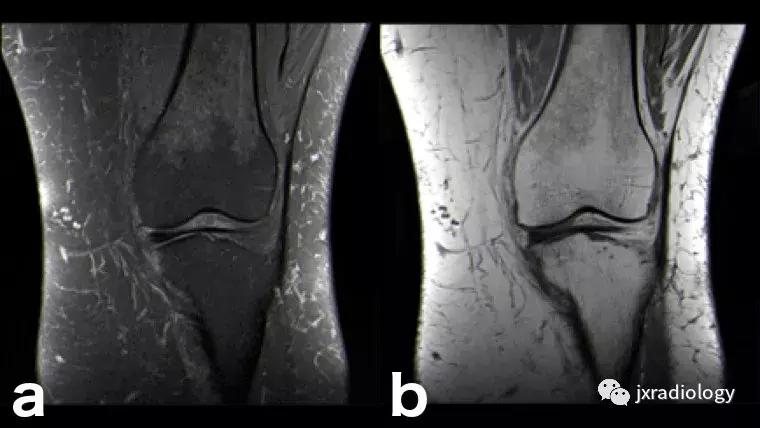

图3:应力(疲劳)骨折:女,25岁,最近在没有适当热身的情况下在健身房参与剧烈运动的冠状位T1WI和STIR图像。她主诉出现双侧内侧胫骨疼痛。在双侧胫骨中,内侧近端应力性骨折是明显的。